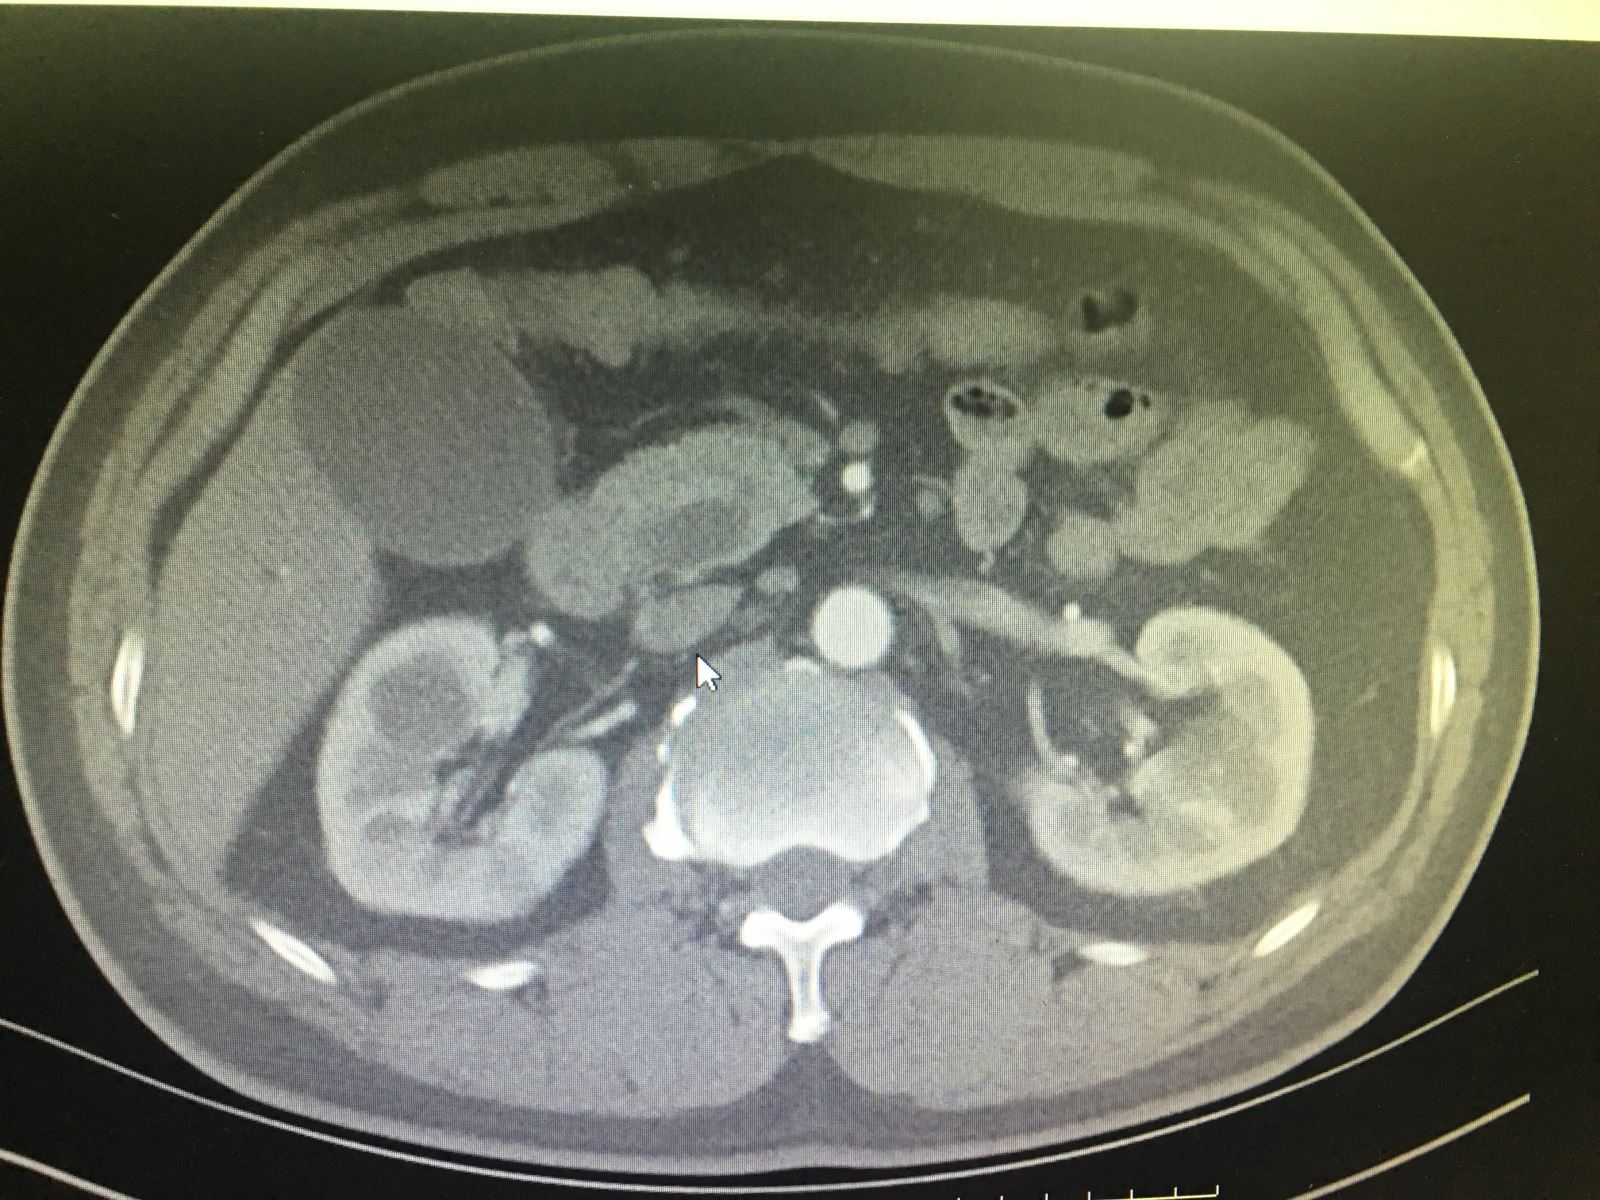

患者徐某,男性,51岁,该患者于3个月前无明显诱因出现巩膜黄染,当时症状较轻,一直未在意,未予诊治。3个月来该患者巩膜呈进行性加重,于半个月前出现全身皮肤黄染,伴瘙痒,尿色加深,呈浓茶水色。期间,曾自行口服保肝药物治疗后,症状并无缓解,于本月14日就诊于通辽市传染病医院,被该院诊断为黄疸应用待查,建议到我院进行进一步诊治,故次日来我院门诊就诊,以“梗阻性黄疸”收入肝胆胰外科。

入院后,通过腹部彩超、腹部增强CT、胰腺核磁增强及MRCP,血常规、肝功能、肿瘤标记物等相关检查,结合检查结果,该患者胆红素升高、肿瘤标记物升高及相关影像资料,该名患者被确诊为壶腹周围癌。与患者及家属进行充分沟通后,由肝胆胰外科主任医师祁向军主任主刀,副主任医师郭雅明医生、副主任医师邵志远医生协助共同完成,采取吉大一院刘亚辉教授的结肠后入路,钩突先行的方法及洪氏一针法胰肠吻合,顺利为患者在全麻下行腹腔镜胰十二指肠切除术。该手术成功为患者切除病灶,术后给患者抗炎、补液等后续治疗,目前该患者各项指标稳定。